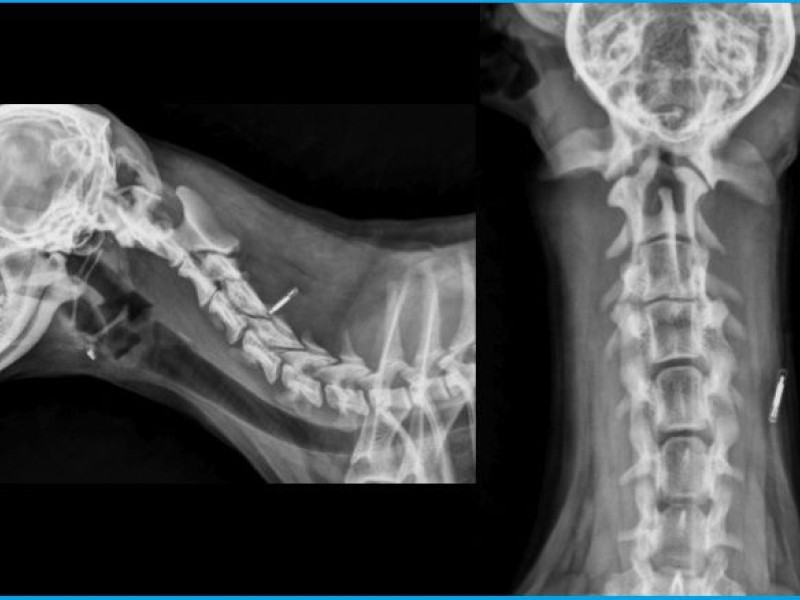

Here under normal radiographs of another yorkshire. Note the decreased space between C1 and C2 and the well developped dens.